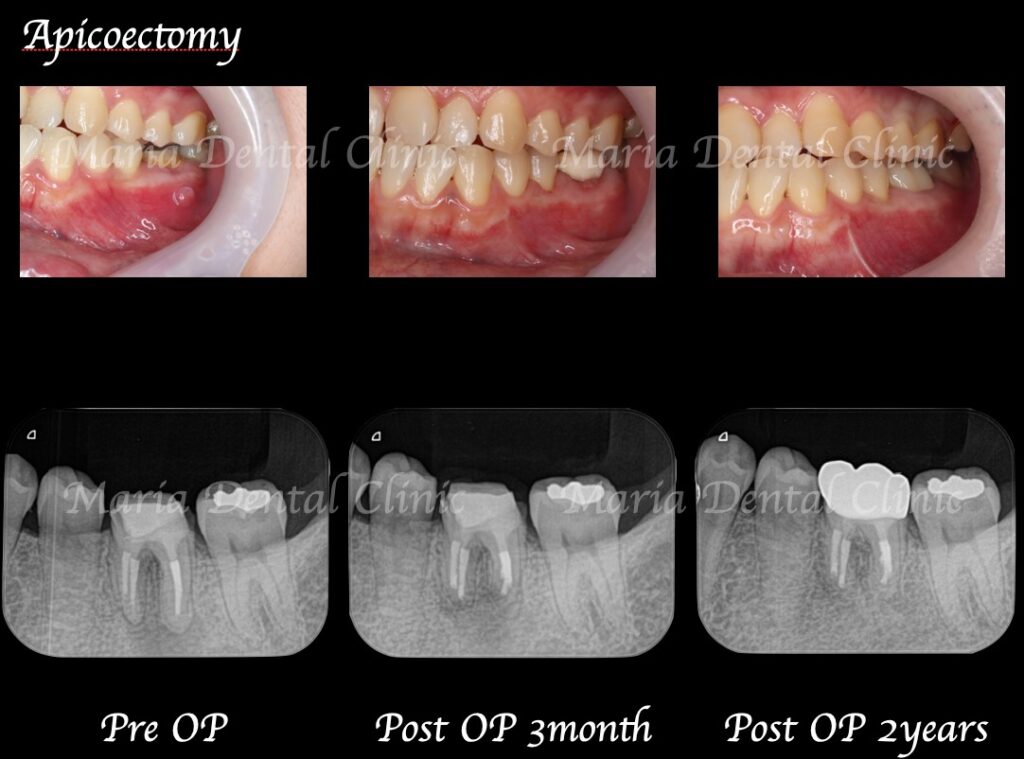

歯根端切除術の症例

【症例】歯根端切除術の失敗をリカバリー(歯根端切除術)

| 治療内容 | 歯根端切除術 |

|---|---|

| 治療期間 | 1日 (消毒、経過観察等は含まない) |

| 治療回数 | 1回 (抜糸、術後3ヶ月後、1年後の経過観察等を除く) |

| 治療費用 | 220,000円(税込)/1本 |

【症例】歯根端切除術により抜歯を覚悟していた歯の保存に成功

| 治療内容 | 再根管治療・歯根端切除術|精密根管治療 |

| 治療期間 | 1ヶ月(精密根管治療後2週間後に外科処置を行った) |

| 治療回数 | 1回(他、抜糸、術後3ヶ月後、経過観察等を除く) |

| 治療費用 | 55,000円(税込) 当院にて精密根管治療後2年内 |